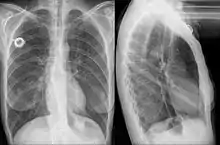

Chest radiograph showing a stent in the distal esophagus